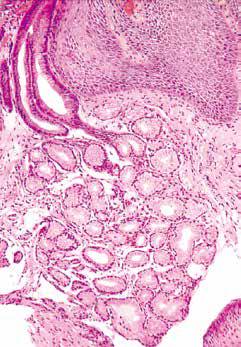

食管中段。食管黏膜由表面的上皮层、中间的固有层及下面的黏膜肌层构成,黏膜肌层由纵行平滑肌束构成。

固有层是黏膜层的非上皮部分,位于黏膜肌层之上,由疏松结缔组织构成,含有脉管结构、散在分布的炎症细胞及黏液分泌性腺体。

食管贲门型腺体弥漫散在分布于整个食管的固有层内,主要见于食管远端和近端部分。这些腺体起润滑作用,以便于食物团块顺利通过食管,这在生理上是必须的。

组织学上,这些腺体位于固有层内,与胃贲门型腺体相似,由分泌中性黏液的细胞组成。

食管贲门型腺体位于固有层内。导管内衬胃小凹样上皮细胞。

黏膜下层由疏松结缔组织构成,含有血管、神经纤维(包括Meissner神经丛)、淋巴管及黏膜下腺。黏膜下腺被认为是口咽部小涎腺的延续,散在分布于整个食管,但在食管上段和下段区域更加集中。

食管中段。食管的黏膜下腺位于黏膜下层内,紧邻黏膜肌层。导管周围和腺体周围慢性炎症可视为正常现象。